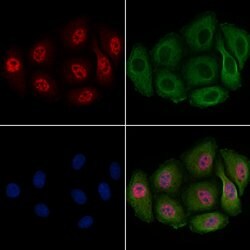

| Immunohistochemistry (Paraffin), Western Blot, Immunocytochemistry | |